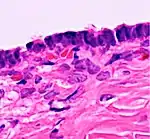

Histopathology

In case an ovarian cyst is surgically removed, a more definite diagnosis can be made by histopathology:

TypeSubtypeTypical microscopy findingsImage

CystadenomaSerous cystadenoma Cyst lining consisting of a simple epithelium, whose cells may be either:[21]

• columnar and tall and contain cilia, resembling normal tubal epithelium

• cuboidal and have no cilia, resembling ovarian surface epithelium